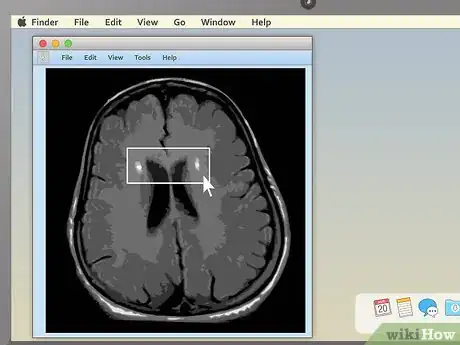

3. 3

Use cross-sectional views to spot abnormalities in brain MRIs. MRIs of the brain tissue are often used to check for brain tumors, abscesses, and other serious problems that can affect the brain. The easiest way to see these things is usually to choose the cross-sectional view, then descend slowly from the top of the head downward. You're looking for anything that's not symmetrical — a dark or light patch that's on one side but not the other is cause for concern.

• Brain tumors often take the form of round, golf ball-like growths in the brain which will usually show up as either bright white or dull grey surrounded by a ring of white. However, other brain problems (like multiple scleroses) can also have a whitish appearance, so this alone may not be a sign of a brain tumor.